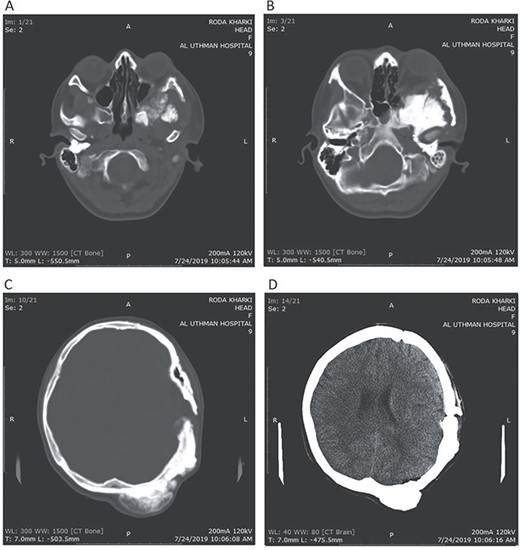

CT head tissue window. A, B. Invasion and destruction of the surrounding tissue. C. Minor shift of the elements of the midline to the right side due to the edema. D. The edema applies pressure to the left lateral ventricle.

A 17-year-old female presented with a history of osteosarcoma that was confirmed after undergoing a surgery to remove an enlarging bone tumor in the left temporal region 2 years ago. She later got pregnant and delivered her child but never got back for a checkup until she was admitted to our hospital with a severe and unresponsive to medication headache that progressed over the course of 6 months and blurred vision that progressed to complete left-sided vision loss. Physical examination revealed a tough and mobile yet fixed at the base 7-cm mass towards the left of the frontal bone. Many more masses were revealed in the left side of the skull including the anterior cranial fossa, orbit, base of the skull and the left part of the occipital region where the previous procedure was performed (Fig. 1). These masses had been increasing in size probably under the influence of pregnancy hormones causing pain that radiated along the orbital and maxillary branches of the left trigeminal nerve. Physical examination and past medical history were otherwise unremarkable. Laboratory tests were all normal, and her family history was negative. Staging studies showed no evidence of distant metastatic disease in the chest, the abdomen and the pelvis. CT scan of the skull revealed a bone-forming non-lytic lesion accompanied by periosteal reaction. This lesion bulges to the outside towards the scalp spreading into both the soft tissues and the inside of the entire left side of the skull with a sunburst-pattern (Figs 2 and 3). Its rims are unsymmetrical and pointy, and it bulges into the left orbit outside the muscles causing exophthalmos with a semi-complete proptosis of the eyeball out of the orbit (Figs 2 and 3). This lesion applies pressure to the left frontal and temporal lobes causing mild edema in both these lobes without invading the brain tissue. This edema in turn applies pressure to the left lateral ventricles (minor shift of the elements of the midline to the right side can be seen on CT) (Fig. 4). Due to the tumor’s wide spread, the surgical procedure was performed in two stages (approximately 6-hour-long each). In the first stage, the bone mass was removed through a procedure of wide skull approach including the frontal, temporal and parietal bones and a removal of the invading part of the temporal muscle. Moreover, the lateral wall and roof of the left orbit were removed, the left optic nerve was dissected free and part of the meninges was removed and replaced with an autogenic patch from the fascia lata. Then, the bone loss was compensated for by using bone cement Synicem VTP (poly methyl methacrylate and Barium sulfate), and the orbit was rebuilt; the eyeball was placed back with noticeable decline of the exophthalmos. In the second stage, a complementary left parietal occipital incision of the previous approach was performed 3 weeks later; the remaining of the frontal and occipital bones was removed, and a partial mastoid surgery was done. Furthermore, the cavernous sinus were revealed and found to be not invaded. Later on, the normal skull shape was restored using the same cement. The histopathology of the lesion revealed proliferation of neoplastic chondroblasts, osteoblasts and spindle-shaped cells. The features are consistent with low-grade chondroblastic osteosarcoma (Fig. 5). The patient did not need ICU admission. She recovered well 3 days after the surgery and was discharged with no deficits. A CT scan that was performed post-operatively revealed that the masses were successfully excised (Figs 6 and 7). At the last follow-up 1 month post-operation, the patient was scheduled to undergo a course of radiotherapy, 60 Gy of radiotherapy in 30 fractions over 4 weeks without chemotherapy, as it is not recommended with low-grade osteosarcoma.